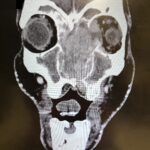

Sinonasal carcinoma is a rare malignancy that often presents with nonspecific symptoms, making early diagnosis challenging. Delayed recognition can lead to disease progression and worse outcomes. This case report emphasizes the importance of early identification, prompt imaging, and multidisciplinary management. A 73-year-old male with a history of anemia and hypertension presented with progressive facial swelling, 20-pound weight loss, and vision loss in the left eye over two months. Initially misdiagnosed with bacterial sinusitis, his symptoms persisted. Examination revealed a proptotic left eye and a large obstructive nasal mass. Computed tomography (CT) and MRI (magnetic resonance imaging) demonstrated a destructive sinonasal mass with skull base and intracranial extension. A biopsy confirmed sinonasal carcinoma, and the patient was started on chemoradiation therapy due to the inoperability of the tumor.

This case underscores the importance of recognizing red flag symptoms such as persistent facial swelling and neurological deficits. Multimodal imaging played a critical role in diagnosis. The literature suggests sinonasal carcinoma is often diagnosed late, reinforcing the need for early suspicion and specialist referral. Sinonasal carcinoma should be considered in patients with persistent facial or nasal symptoms. Timely imaging, biopsy, and interdisciplinary care are essential for optimizing outcomes.